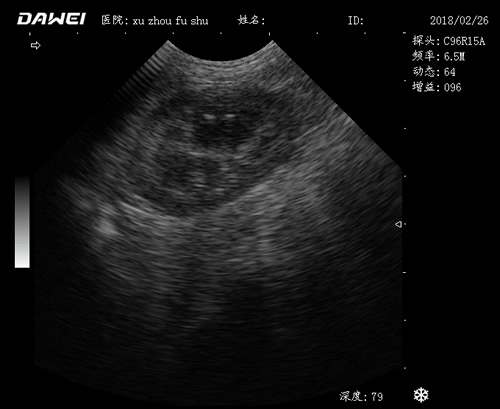

應(yīng)用范圍:

·中小動(dòng)物的肝、膽,脾、腎、膀胱、子宮、妊娠等各組織器官的檢查和病變的診斷